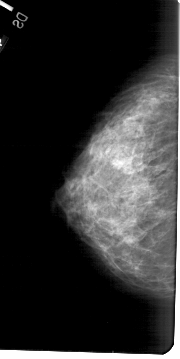

A_1677_1.LEFT_MLO

LEFT_MLO LINES 5491 PIXELS_PER_LINE 2536 BITS_PER_PIXEL 12 RESOLUTION 43.5 NON_OVERLAY